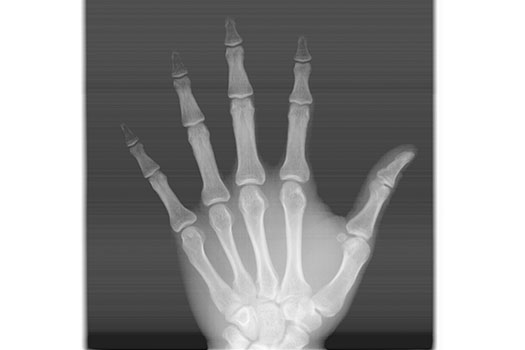

CARPAL

Sirve para determinar la madurez esqueletal del paciente. Se utiliza para Ortopedia, Implantes y es solicitada constantemente por los médicos endocrinólogos.